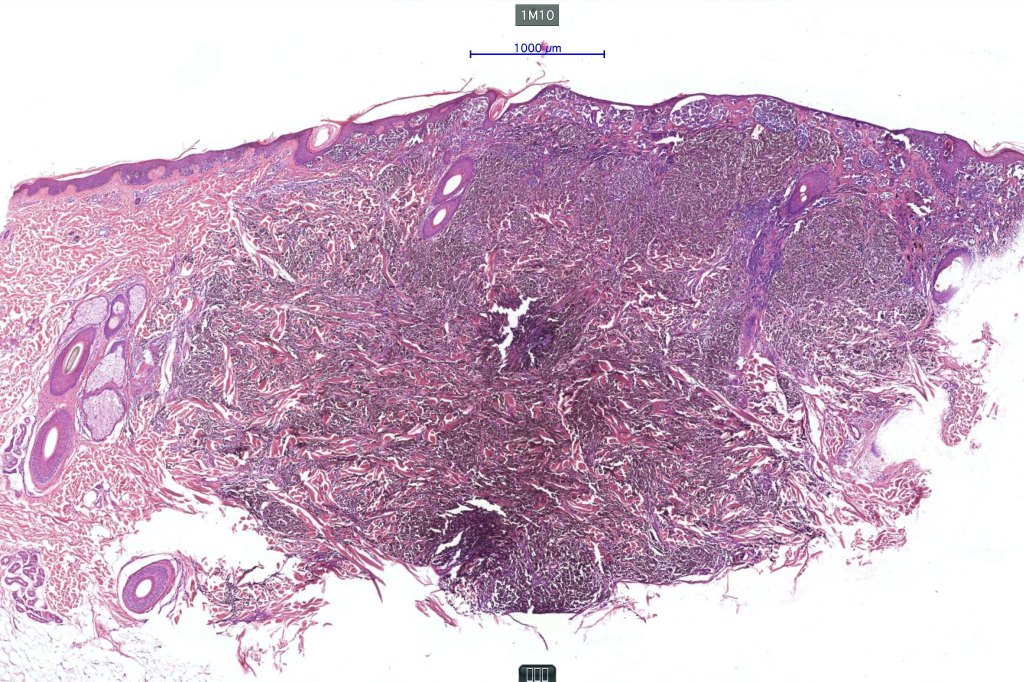

1.typical melanoma in the superficial aspect overlying a deep penetrating nevus-like deeper component

2. typical epithelioid melanoma in the superficial aspect associated with very marked perivascular and appendageal spread giving rise to a plexiform appearance

4. melanoma which shows a deep penetrating architecture although the cytology remains epithelioid throughout